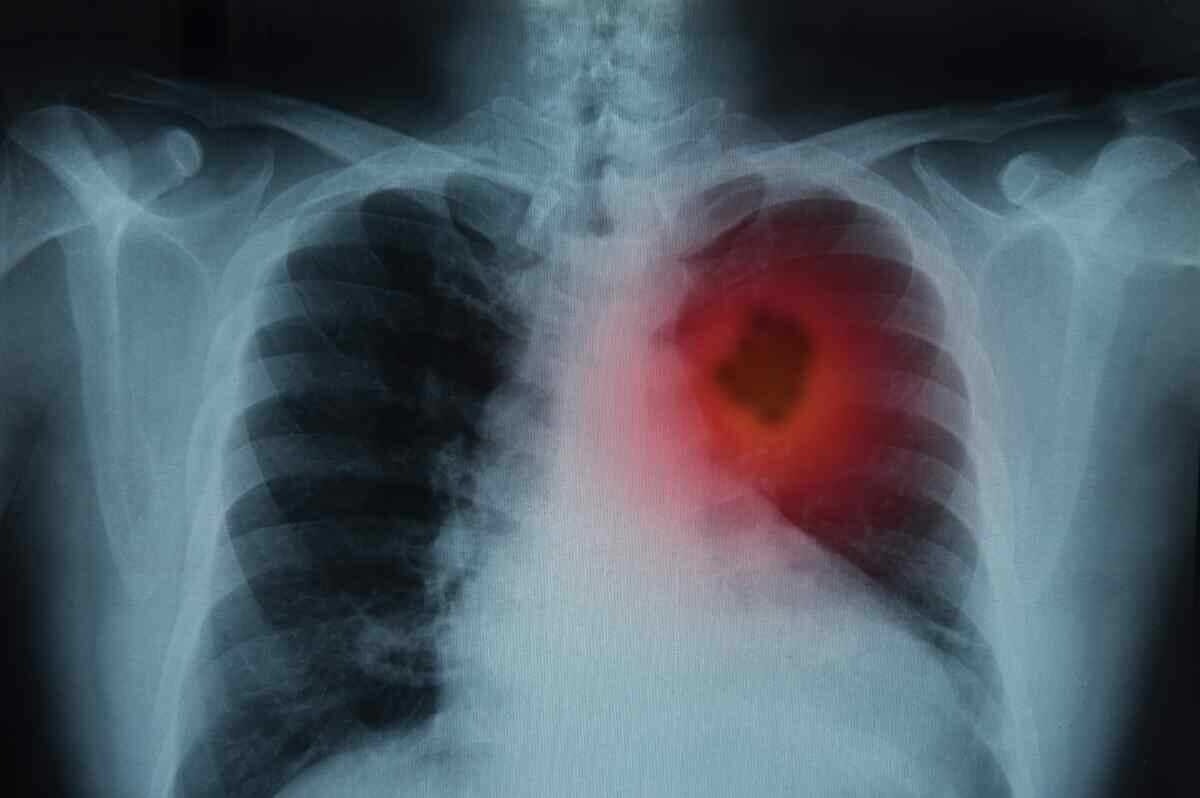

Akciğer kanseri olan bireylerde göğüs kafesi ve kalp zarı içinde sıvı birikimi belirtileri ortaya çıktığında hemen uzman bir hekime başvurmak önemlidir.